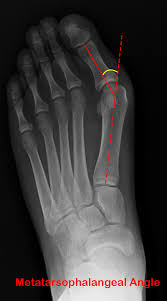

Hallux Valgus, commonly known as Bunions, is where the big toe excessively angles (>15 degrees) towards the rest of the toes. See the xray. This can lead to a bony lump on the side of the foot and osteoarthritic changes to the joint. You can sometimes get an overlaying bursa (sac of fluid) to the joint which can become very inflamed.